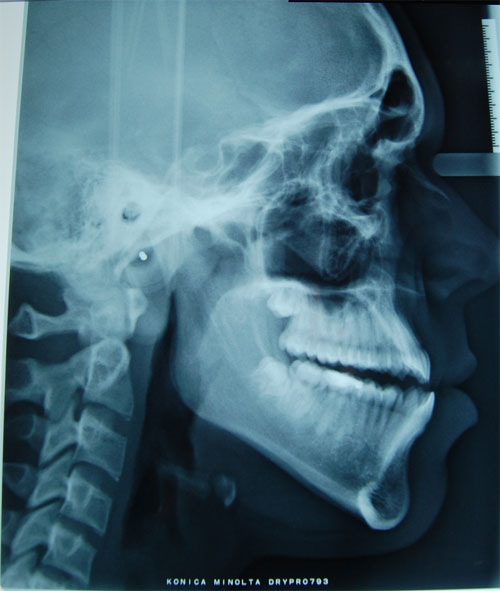

Si è presentato nel mio studio un paziente, di anni 19, con la necessità di risolvere la sua grave terza classe scheletrica. Tra le alternative proposte, il paziente decideva di sottoporsi a intervento chirurgico prima e dopo il quale è stato necessario un trattamento ortodontico tradizionale.

Inizialmente si procede con un’espansione dell’arcata superiore e un allineamento superiore e inferiore. Successivamente si procede all’intervento chirurgico, consistente nella riduzione del ramo mandibolare e spostamento in avanti del mascellare superiore.

Dopo l’intervento si è effettuato un ulteriore allineamento per migliorare l’ingranaggio delle arcate dentarie, oltre all’utilizzo di elastici di 2° classe, specialmente nelle fasi immediatamente successive alla chirurgia.

Lo sbandaggio è stato effettuato circa un anno dopo l’intervento. Al paziente è stato consegnato un posizionatore da utilizzare a permanenza durante la notte.

Per sua scelta il paziente ha preferito non correggere l’allineamento della linea mediana e ha deciso di indossare a permanenza un posizionatore notturno da utilizzare per contenzione e per il click bilaterale all’articolazione temporomandibolare preesistente, che è rimasto dopo l’intervento.